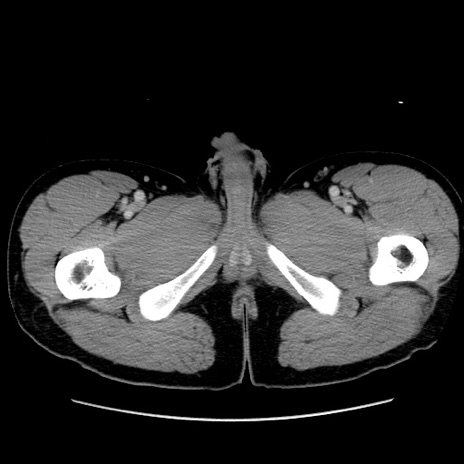

症例36(横断像)

【症例】20歳代 男性

【主訴】心窩部痛

【現病歴】今朝より上腹部痛あり。一旦軽快していたが再度出現したため救急要請。昨日夕に白身の魚を含む刺身を食べた。

【身体所見】BP 136/89mmHg、HR 74/min、BT 37.0℃、腹部:膨満、軟、心窩部に圧痛あり。反跳痛なし、筋性防御なし、腸雑音やや亢進あり。

【データ】WBC 17700、CRP 0.48